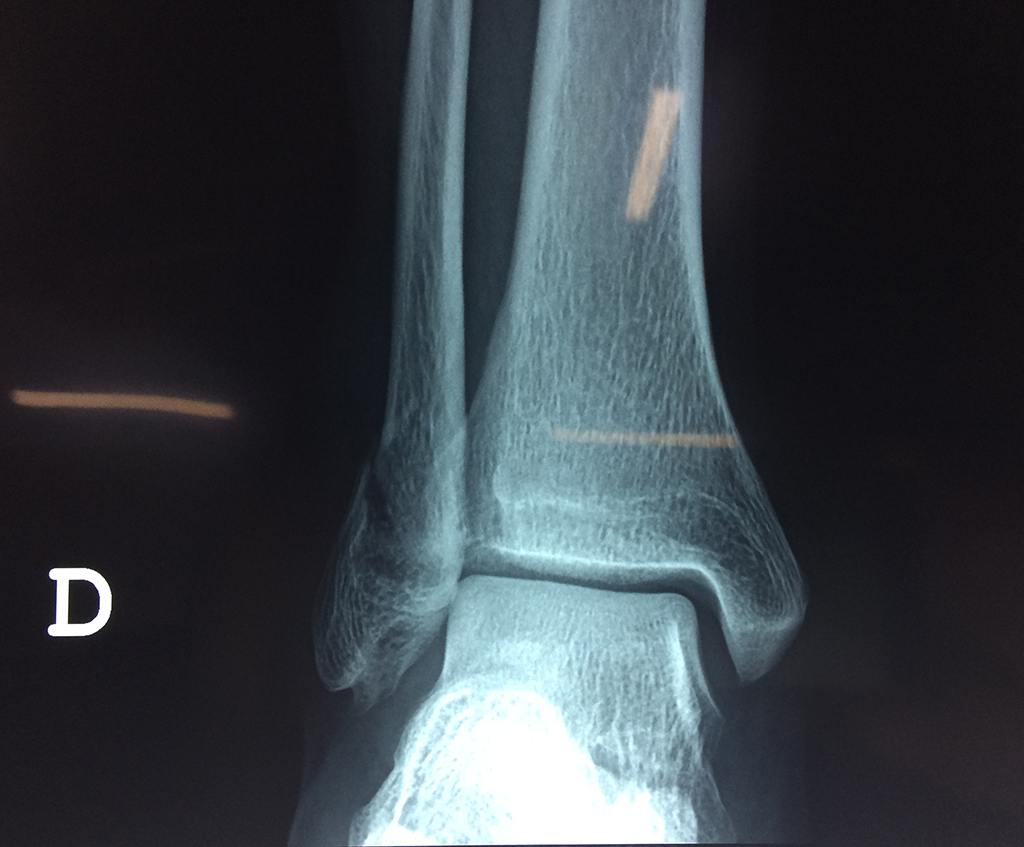

Una fractura de tobillo es la rotura de uno o más de los huesos del tobillo. Estas fracturas pueden ser:

Algunas fracturas de tobillo pueden requerir cirugía si:

Cuando se necesita cirugía, es probable que esta implique el uso de clavijas de metal, tornillos o placas para sostener los huesos en su lugar mientras la fractura se consolida. Los elementos de soporte pueden ser temporales o permanentes.